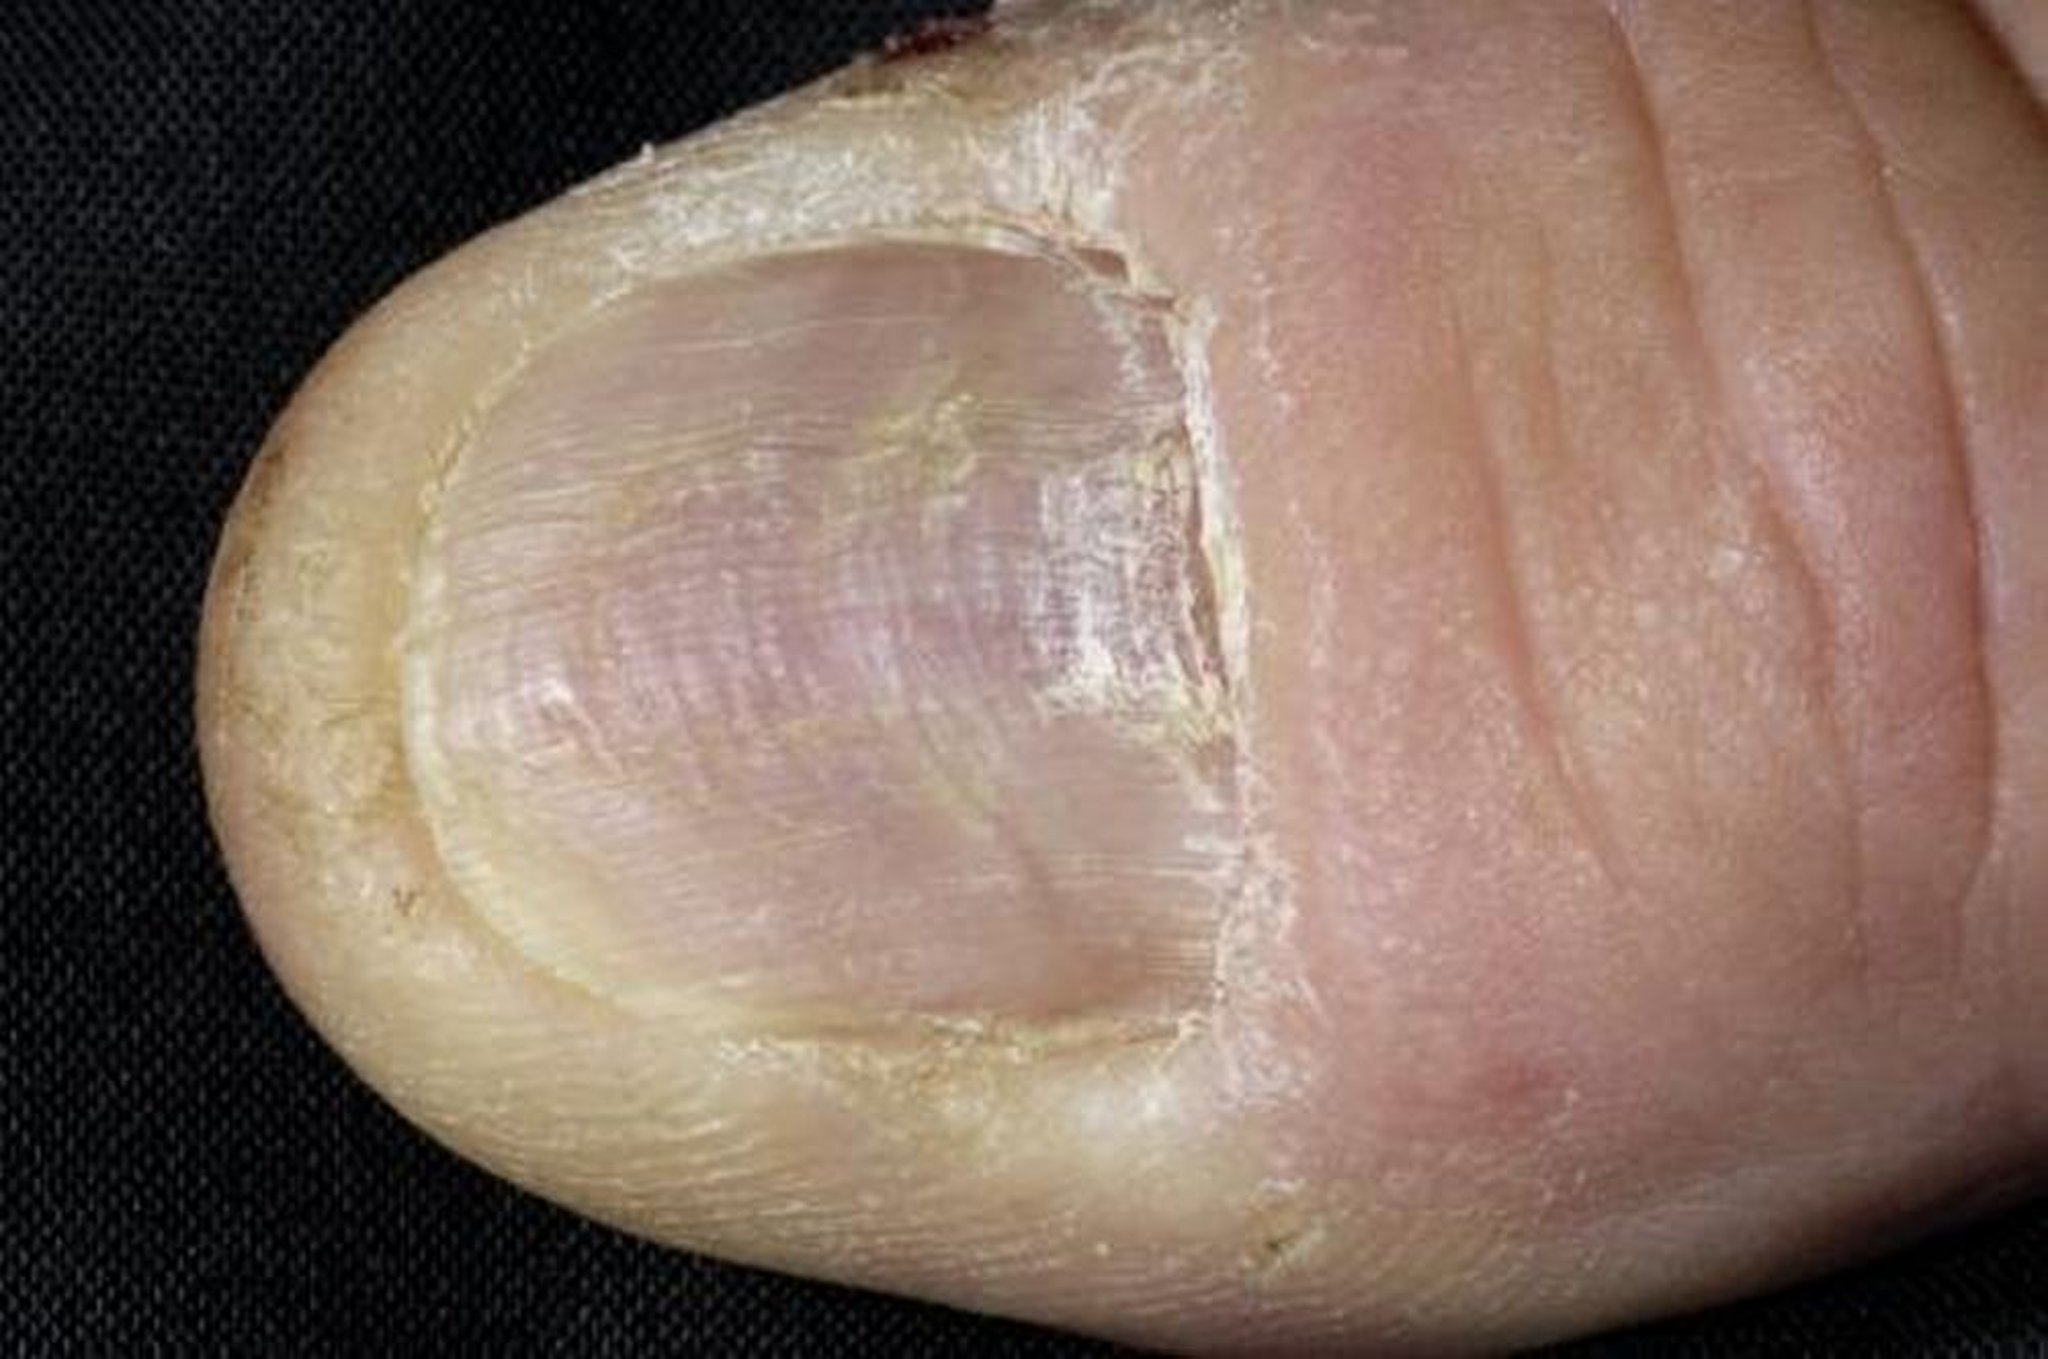

Liquen plano de la uña

Esta fotografía muestra crestas longitudinales en la uña del pulgar de un paciente con liquen plano.